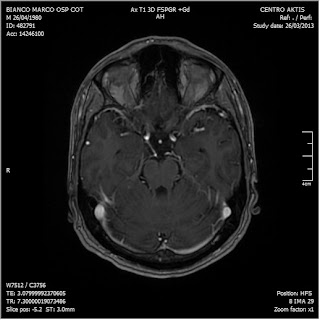

26/03/2013. Ritorna a controllo al Cotugno dove effettua nuova RM con MdC

• lesioni non visibili con il contrasto

RM del 26/3/2013